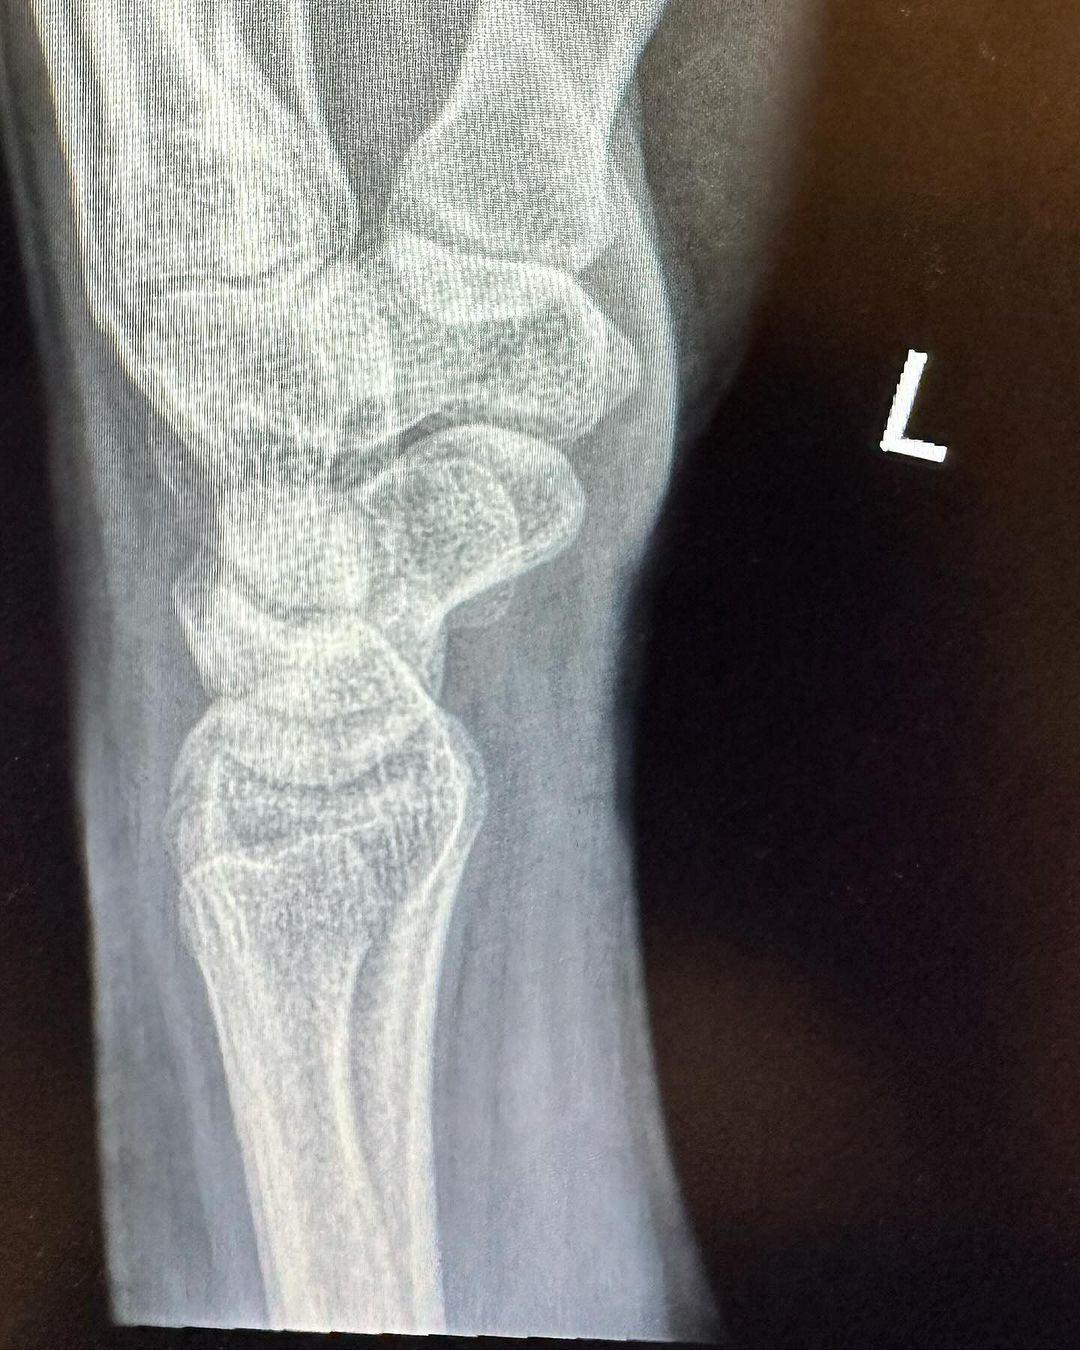

Pelakon, Azira Shafinaz berkongsi berita duka apabila tulang pergelangan tangannya mengalami keretakan gara-gara terjatuh ketika menjalani penggambaran sebuah drama.

Menurut pemilik nama sebenar Azira Shafinaz Ramlan, 33, meskipun beliau terpaksa dikejarkan ke jabatan kecemasan sebuah hospital, tiada kecederaan serius yang perlu dirisaukan.

“Alhamdulillah tiada kecederaan serius, cuma retak yang sangat kecil (hairline fracture) bahagian tulang pergelangan tangan. Tolong doakan saya segera pulih,” tulis beliau menerusi hantaran di Instagram.